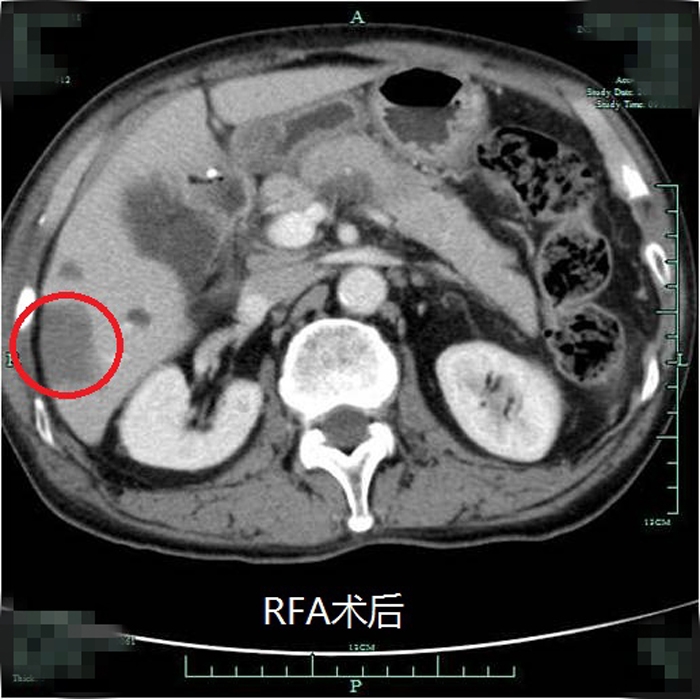

典型射頻治療患者術(shù)前術(shù)后效果對比(非該尾狀葉患者)

??? 近年來,我院肝膽外科在肝癌治療的綜合體系方面更加合理完善,肝癌射頻消融術(shù)已逐步成為繼肝癌切除術(shù)、經(jīng)皮選擇性肝動脈栓塞化療(TACE)后常規(guī)開展的治療手段。自2012年開展此項技術(shù)以來,針對常規(guī)部位的肝癌射頻消融均取得了非常理想的效果。但由于尾狀葉腫瘤位置較深,周圍大血管包繞,不僅手術(shù)難度大,能否安全徹底地對該部位腫瘤進行射頻消融也具有一定的挑戰(zhàn)性。此次在超聲影像等多學科的團隊協(xié)作下,成功完成了尾狀葉腫瘤的射頻消融術(shù)。